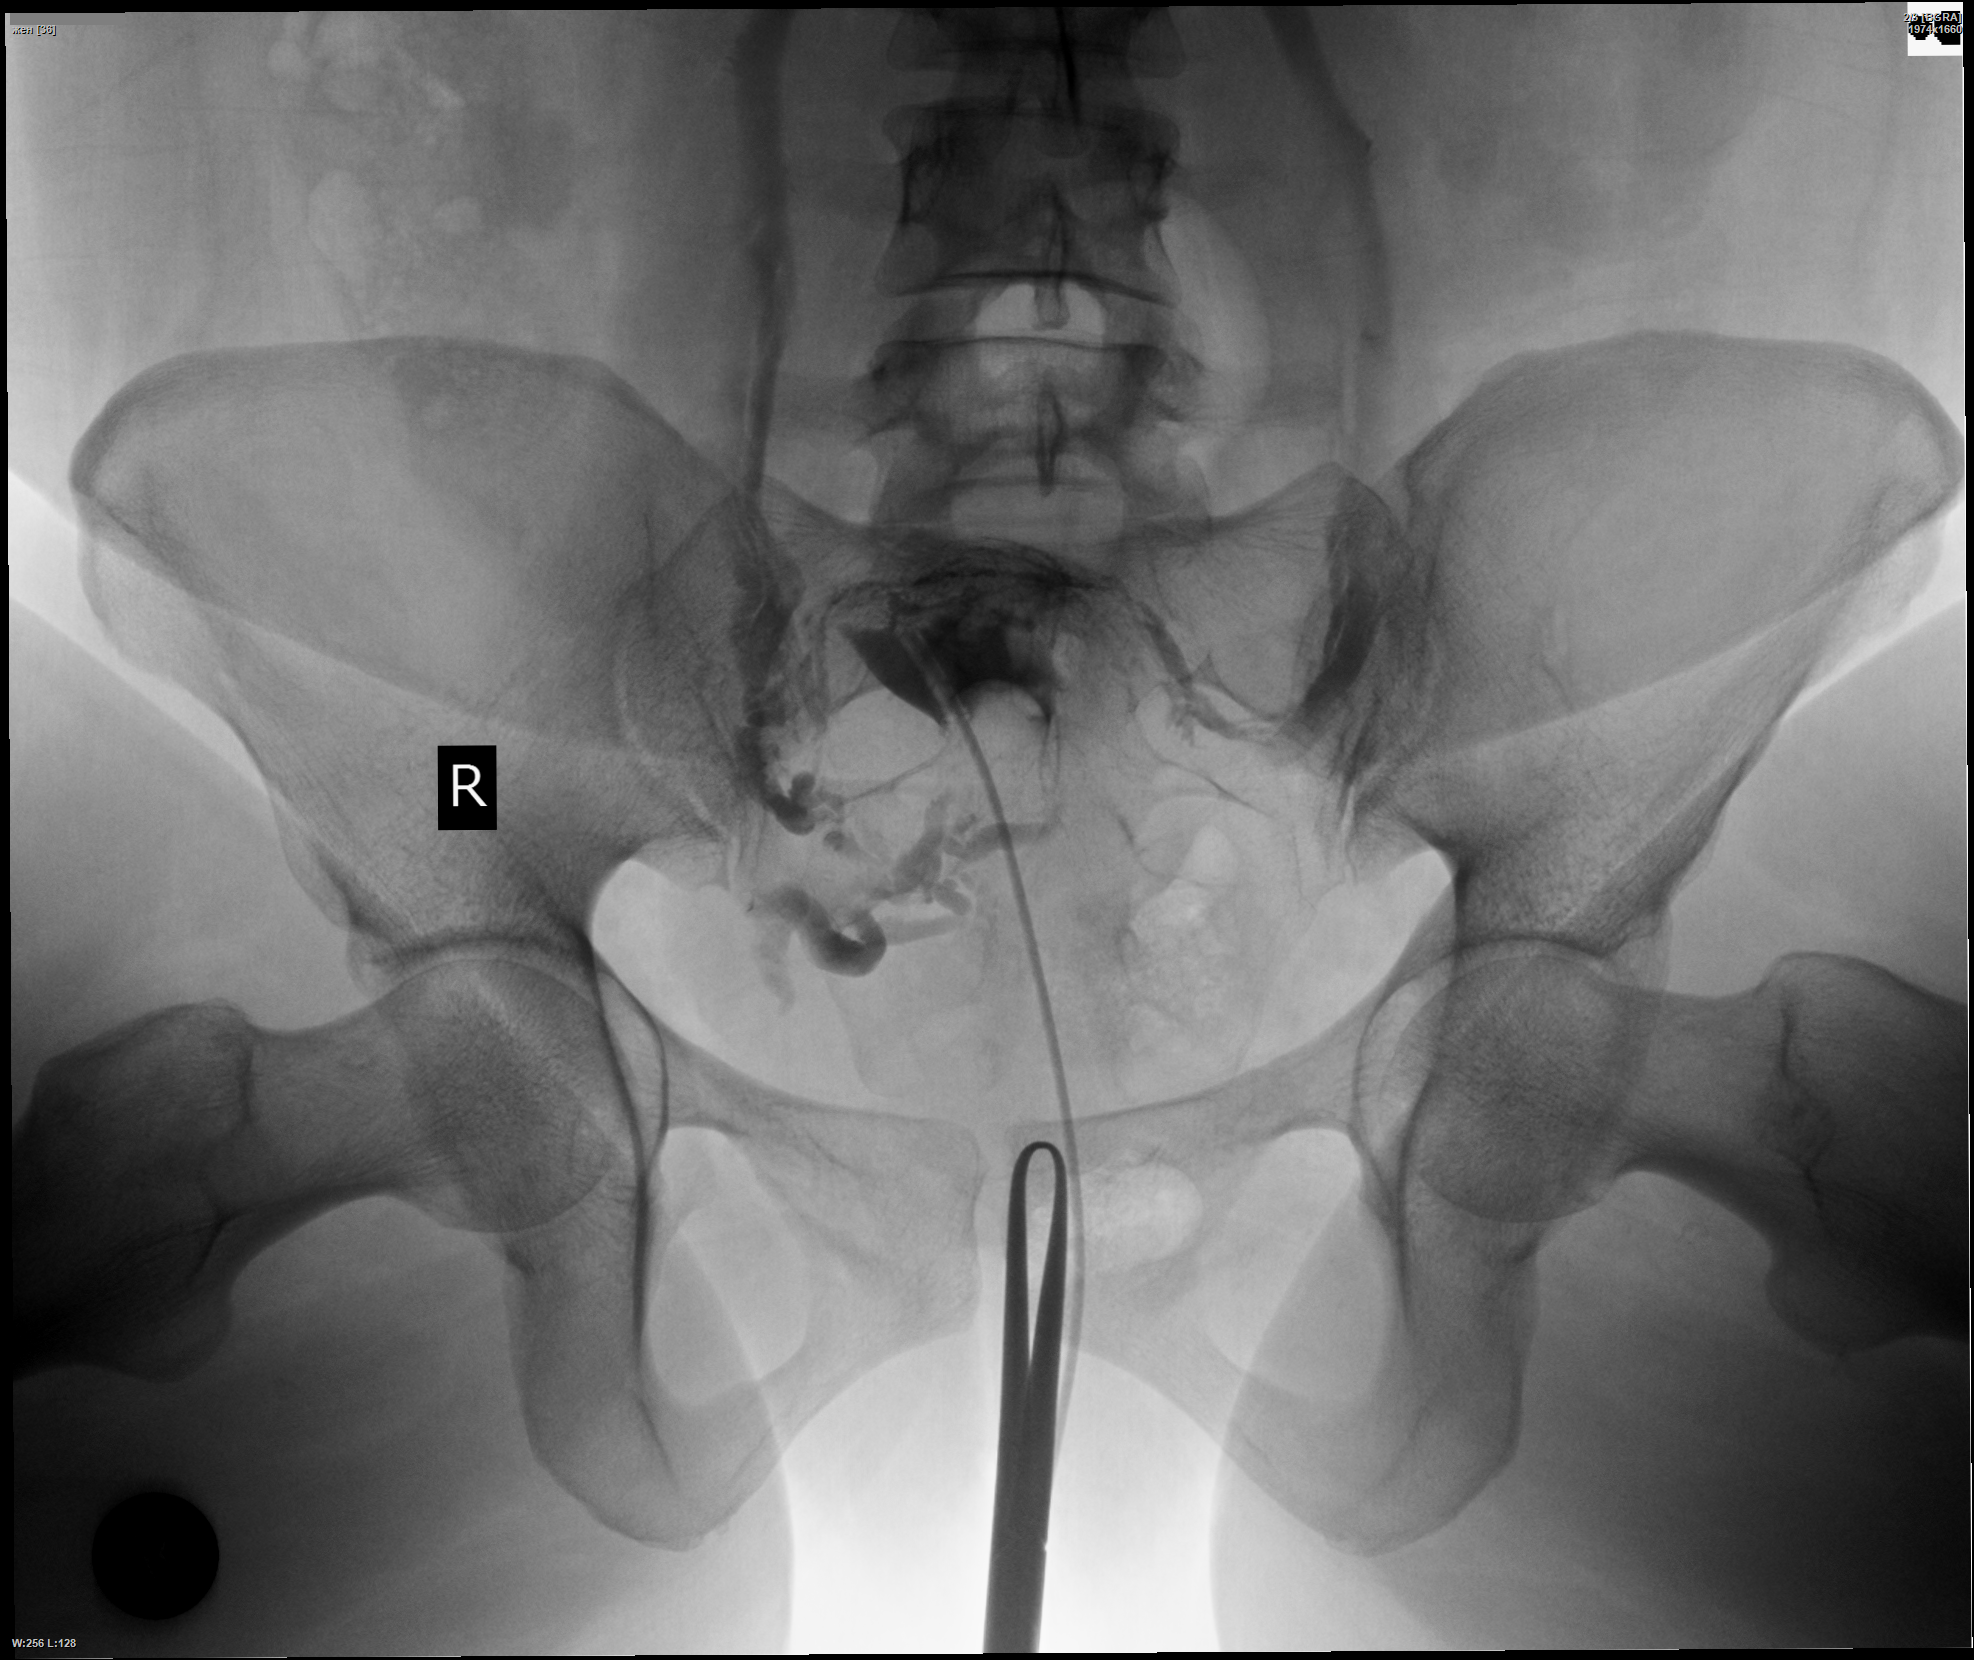

Медицинские снимки: Проходимость маточных труб

Раздел: Кадры-подсказки